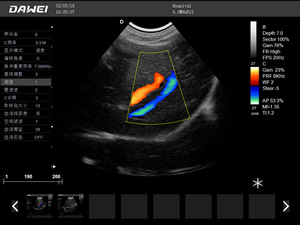

·支持彩色多普勒、頻譜多普勒、能量多普勒、連續多普勒等成像技術

·實時三維成像技術